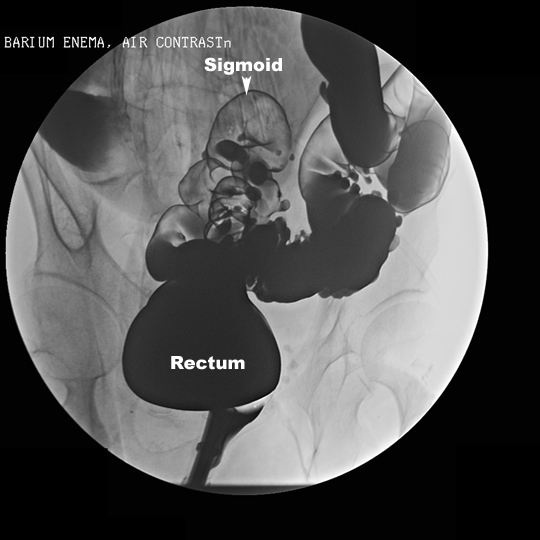

- On X-ray, the colon is

identified by the sacculations called haustra scattered all along the colon.